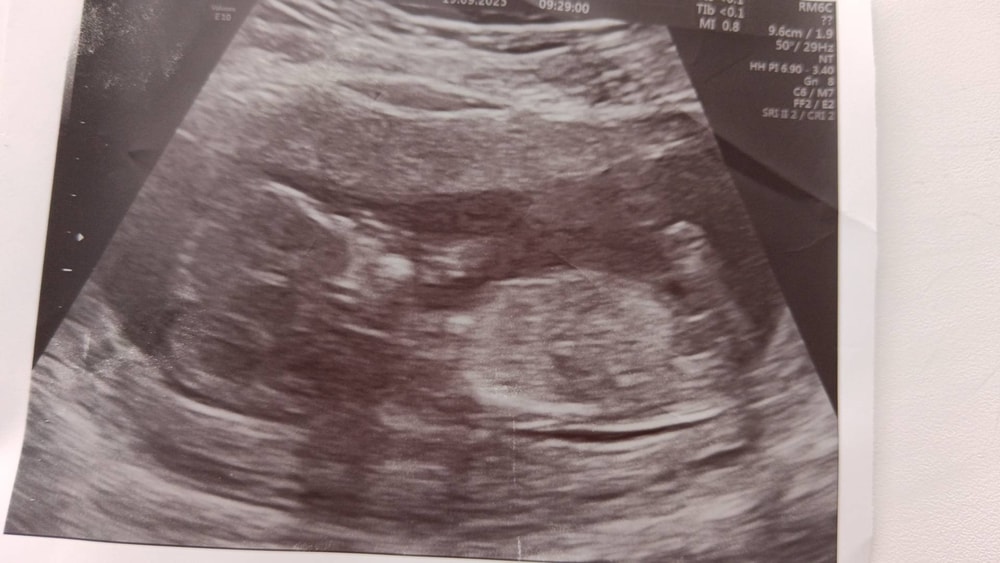

Абакумова Анна в Благополучная беременность 2 месяца Кто на узи, мальчик или девочка УЗИ, КТГ, доплер Кого вы видите? 😍 Посмотрите еще 20 записей на эту тему Отменить Ответить Ирина Понарошку А мне кажется мальчик.там как будто 🍌 торчит 09.10.2025 Ответить Анастасия На мальчишку похож) 09.10.2025 Ответить Виктория Плохо видно но скорее девочка 09.10.2025 Ответить Анютка А мне кажется мальчишка 09.10.2025 Ответить Я Девочка 09.10.2025 Ответить Мария Голосую за девочку! 09.10.2025 Ответить Вес плода в 30 недель Первое узи Чаты Беременных Выберите чат: Январята-2026 Февралята-2026 Мартята-2026 Апрелята-2026 Майчата-2026 Июнята-2026 Июлята-2026 Августята-2026